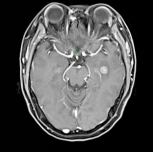

治疗后,如果患者病情稳定或者没有新出现症状,建议每3个月接受核磁共振检查,以早期发现颅内病灶的进展。